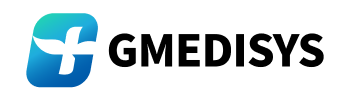

Orchestrating End-to-End Pathology Workflows with Universal Hardware and System Compatibility

AI-powered diagnostic platform transforms pathology into a seamless, interconnected workflow—spanning digital slide scanning, AI-augmented diagnosis, and automated report delivery—while ensuring universal compatibility with leading hardware devices and hospital information systems.

Hardware Agility: Bridging Diverse Scanning Ecosystems

The AI-powered diagnostic platform achieves robust interoperability with a vast spectrum of digital slide scanners, covering:

Global industry leaders: Philips, Zeiss, Leica Biosystems, Roche (ScanIm platform).

Niche specialists: 3DHISTECH (Europe), d-matrix (precision imaging), KFBIO (innovative optics).

Regional innovators: Motic, Unic

(Asia-Pacific), and more.

Crucially, it extends beyond third-party devices: we also support our own AI-optimized reagents, purpose-built scanners, and specialized microscopes. This means hospitals can either leverage existing infrastructure (preserving capital investments) or adopt tailored tools for enhanced performance—no forced hardware overhauls required.

System Integration: Syncing with Pathology IT Landscapes

On the software front, our AI-powered diagnostic platform integrates flawlessly with pathology information management systems (PIMS) and hospital IT ecosystems.

This eliminates manual bottlenecks:

Scanned slides flow directly into AI-driven analysis.

Pathologists’ diagnoses sync instantly with the PIMS.

Finalized reports auto-distribute to clinicians, embedded in the hospital’s core workflow.

Every step—from slide scanning to report delivery—operates as a unified, frictionless chain, cutting administrative delays and ensuring diagnostic insights reach care teams faster.

The Unified Advantage: Efficiency Without Compromise

By connecting hardware diversity, AI analysis, and system connectivity, we:

Streamlines workflows: Reduces manual handoffs, accelerating time-to-diagnosis.

Protects investments: Lets hospitals keep trusted devices while adding AI capabilities.

Empowers experts: Frees pathologists from repetitive tasks to focus on complex cases.

In short, we don’t just “add AI” to pathology—it weaves AI into the entire diagnostic journey, harmonizing with existing tools and systems to deliver faster, more consistent care. The future of pathology isn’t about replacing hardware or workflows—it’s about unifying them.